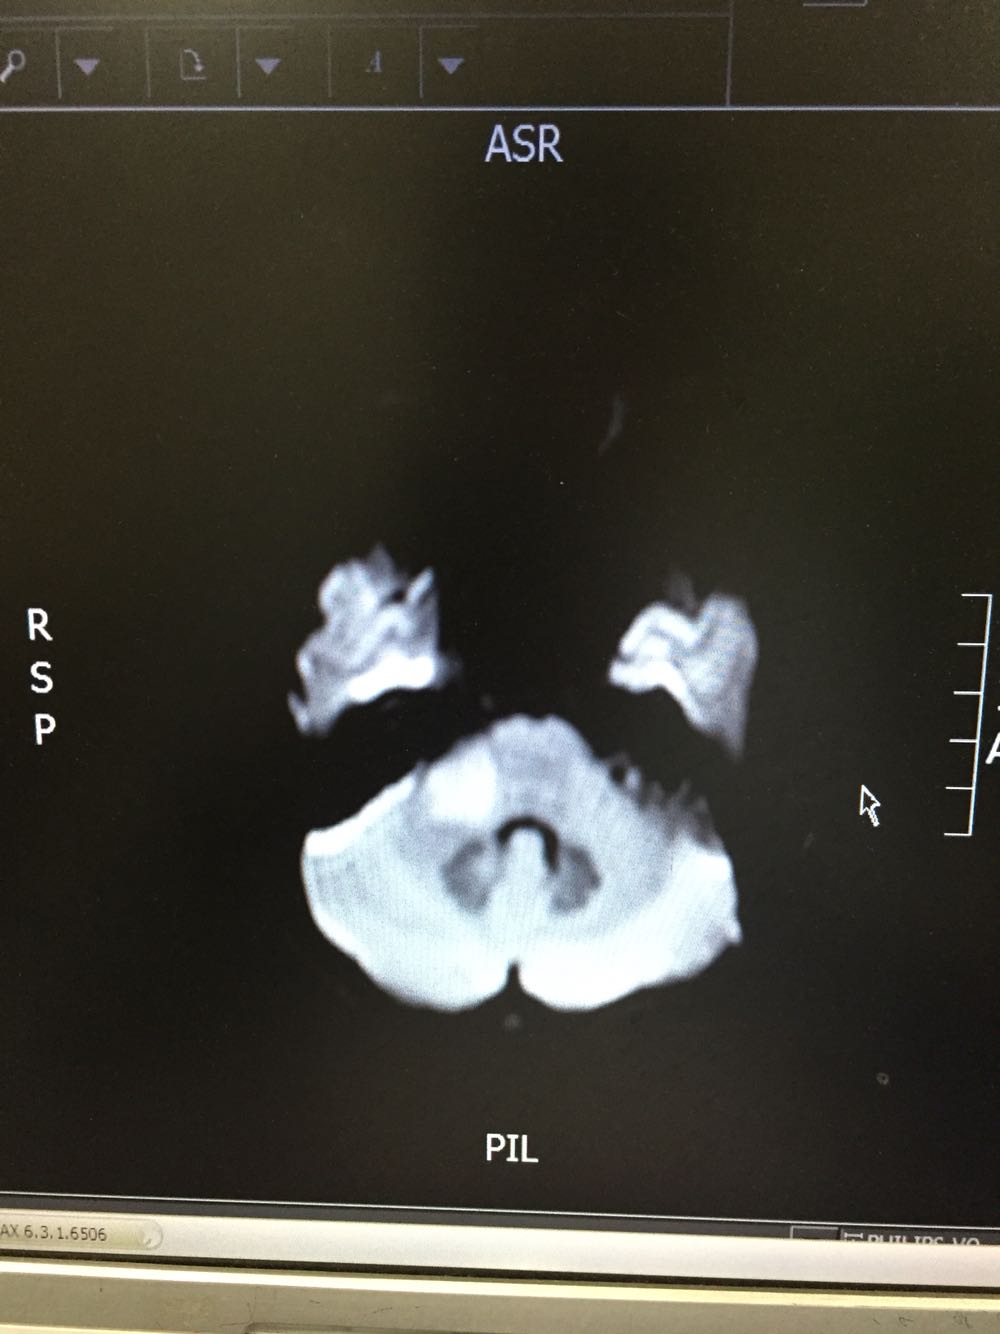

女,35岁,因“右侧肢体无力伴语笨9日”由门诊收入病房。病例特点:1.既往史:青年女患,既往否认高血压病史,否认糖尿病及冠心病史,否认药物、食物过敏史。2.现病史:该患者于入院前9日始出现右侧肢体无力,伴语笨,伴有恶心、呕吐,不伴有头痛,偶有头晕,不伴有尿便障碍,不伴有抽搐发作,为求进一步诊治而来我院。

查体:体温:36。5℃,脉搏:70次/分,呼吸:18次/分,血压:121/79mmHg,神志清楚,言语流利,查体合作,双侧瞳孔等大同圆,对光反射存在,双眼活动自如,鼻唇沟对称,伸舌居中,右侧肢体肌力4级,肌张力正常,腱反射对称,双侧感觉对称,右下肢Babinski征(+)、Chaddock征(+)、颈强(-),克氏征(-)。 脑脊液免疫球蛋白A0.003g/L 抗酸杆菌、墨汁染色阴性,余脑脊液化验未见异常。脑脊液外观无色透明

桥脑脱髓鞘病变可能性大甲强龙冲击治疗

初始考虑青年脑梗死待磁共振增强回报后考虑能否占位可能脑功能成像及脑脊液结果回报后考虑桥脑脱髓鞘病变可能性大,给予甲强龙冲击治疗,冲击治疗后患者症状逐渐好转,右侧肢体肌力出院时5-级。